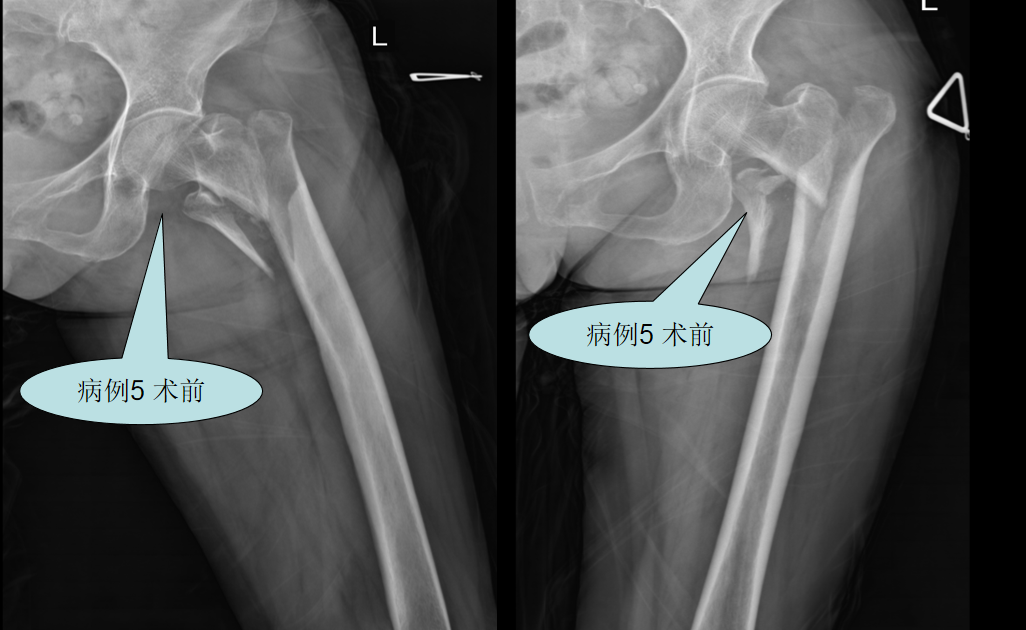

【病例三】